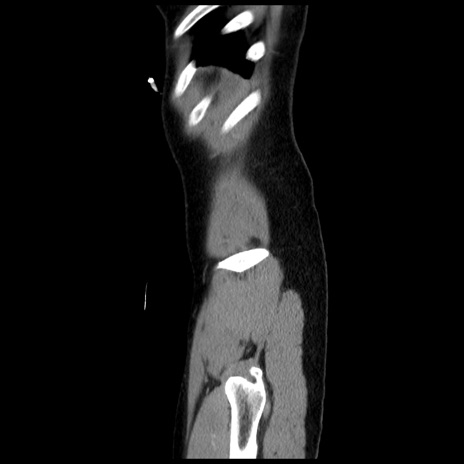

横断像